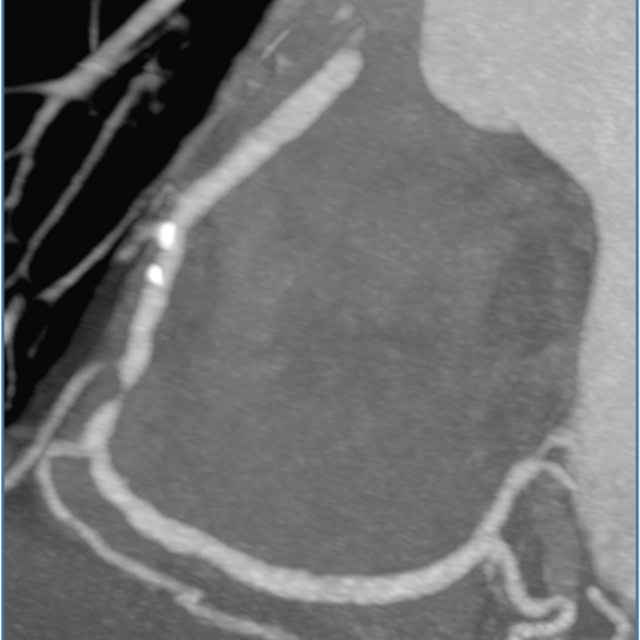

Beginning in 2026, interventional cardiology fellows will be offered formal training in coronary CTA, relying on structured CT reading sessions, lectures, and imaging case files to achieve Level II cardiac CT proficiency and qualification for the cardiac CT boards upon completion of interventional training. As our field shifts away from traditional stress imaging and towards coronary CTA as the preferred non-invasive method of assessment of CAD, there are emerging needs for interventional cardiologists to master coronary CTA for anatomic assessment of CAD, physiologic assessment with FFRCT and myocardium at-risk, morphologic assessment of plaque burden and characterization, and advanced planning of PCI for calcified plaque, bifurcation lesions, and CTO. Since ad-hoc PCI has become embedded in interventional practice, PCI planning with CTA allows precise equipment selection; reduces procedural time and radiation exposure to the patient and staff; allows the best opportunity for risk assessment for the patient and family, even before the patient goes to the cardiac catheterization laboratory. The Interventional Cardiology Fellowship Program at William Beaumont University Hospital is the first to offer formal cardiac CT training as part of its curriculum.